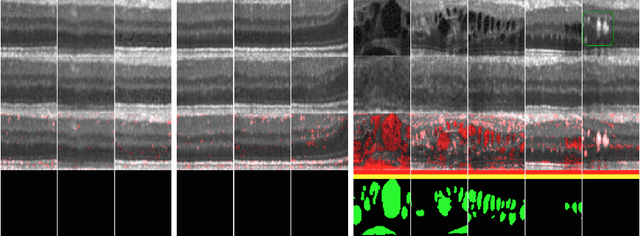

Abstract:Diagnosis and treatment guidance are aided by detecting relevant biomarkers in medical images. Although supervised deep learning can perform accurate segmentation of pathological areas, it is limited by requiring a-priori definitions of these regions, large-scale annotations, and a representative patient cohort in the training set. In contrast, anomaly detection is not limited to specific definitions of pathologies and allows for training on healthy samples without annotation. Anomalous regions can then serve as candidates for biomarker discovery. Knowledge about normal anatomical structure brings implicit information for detecting anomalies. We propose to take advantage of this property using bayesian deep learning, based on the assumption that epistemic uncertainties will correlate with anatomical deviations from a normal training set. A Bayesian U-Net is trained on a well-defined healthy environment using weak labels of healthy anatomy produced by existing methods. At test time, we capture epistemic uncertainty estimates of our model using Monte Carlo dropout. A novel post-processing technique is then applied to exploit these estimates and transfer their layered appearance to smooth blob-shaped segmentations of the anomalies. We experimentally validated this approach in retinal optical coherence tomography (OCT) images, using weak labels of retinal layers. Our method achieved a Dice index of 0.789 in an independent anomaly test set of age-related macular degeneration (AMD) cases. The resulting segmentations allowed very high accuracy for separating healthy and diseased cases with late wet AMD, dry geographic atrophy (GA), diabetic macular edema (DME) and retinal vein occlusion (RVO). Finally, we qualitatively observed that our approach can also detect other deviations in normal scans such as cut edge artifacts.